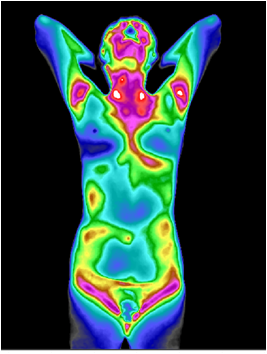

红外热成像非常灵敏,它能极其敏感地接收人体细胞新陈代谢所产生的热辐射(小于0.025 ℃ ),并通过特有的成像和“由表及里”的病灶凸显层析技术,显示出人体内异常热源的分布、深度、强度、形态及走势。从而全面、真实、动态地反映由人体代谢热所表达的健康状况和疾病信息,再与其他技术手段结合,有利于临床作出更加真实、准确、早期的诊断和疗效评估。

图4 阳虚体质红外热成像图